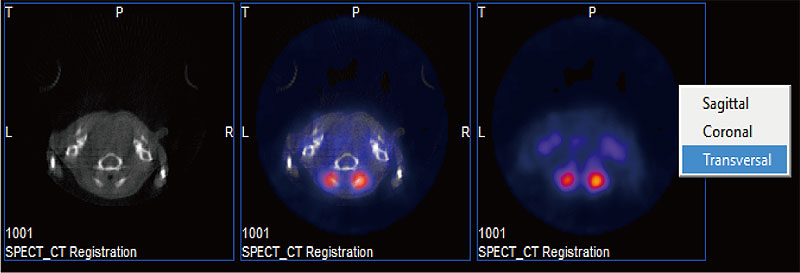

同一スライスのフュージョン前後の画像が、横並びに表示されます。

矢状面・冠状面・横断面を切替えることができます。

画像は、矢状面・冠状面・横断面それぞれのスライス表示で、 各画面内の3つの画像は、左から順に、CT画像(リファレンス画像)、CT/SPECTフュージョン画像、SPECT画像(入力画像)です。

マルチ表示:矢状面

矢状面

マルチ表示:冠状面

冠状面

マルチ表示:横断面

横断面